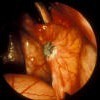

Endometriosis lesions*